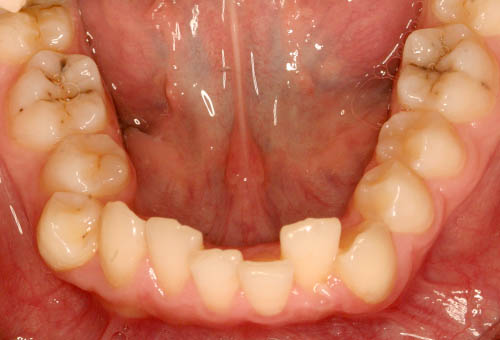

Фотографии 1

летней пациентки

, до и после 16 месяцев лечения

Улучшение состояния мягких и твердых тканей полости рта.